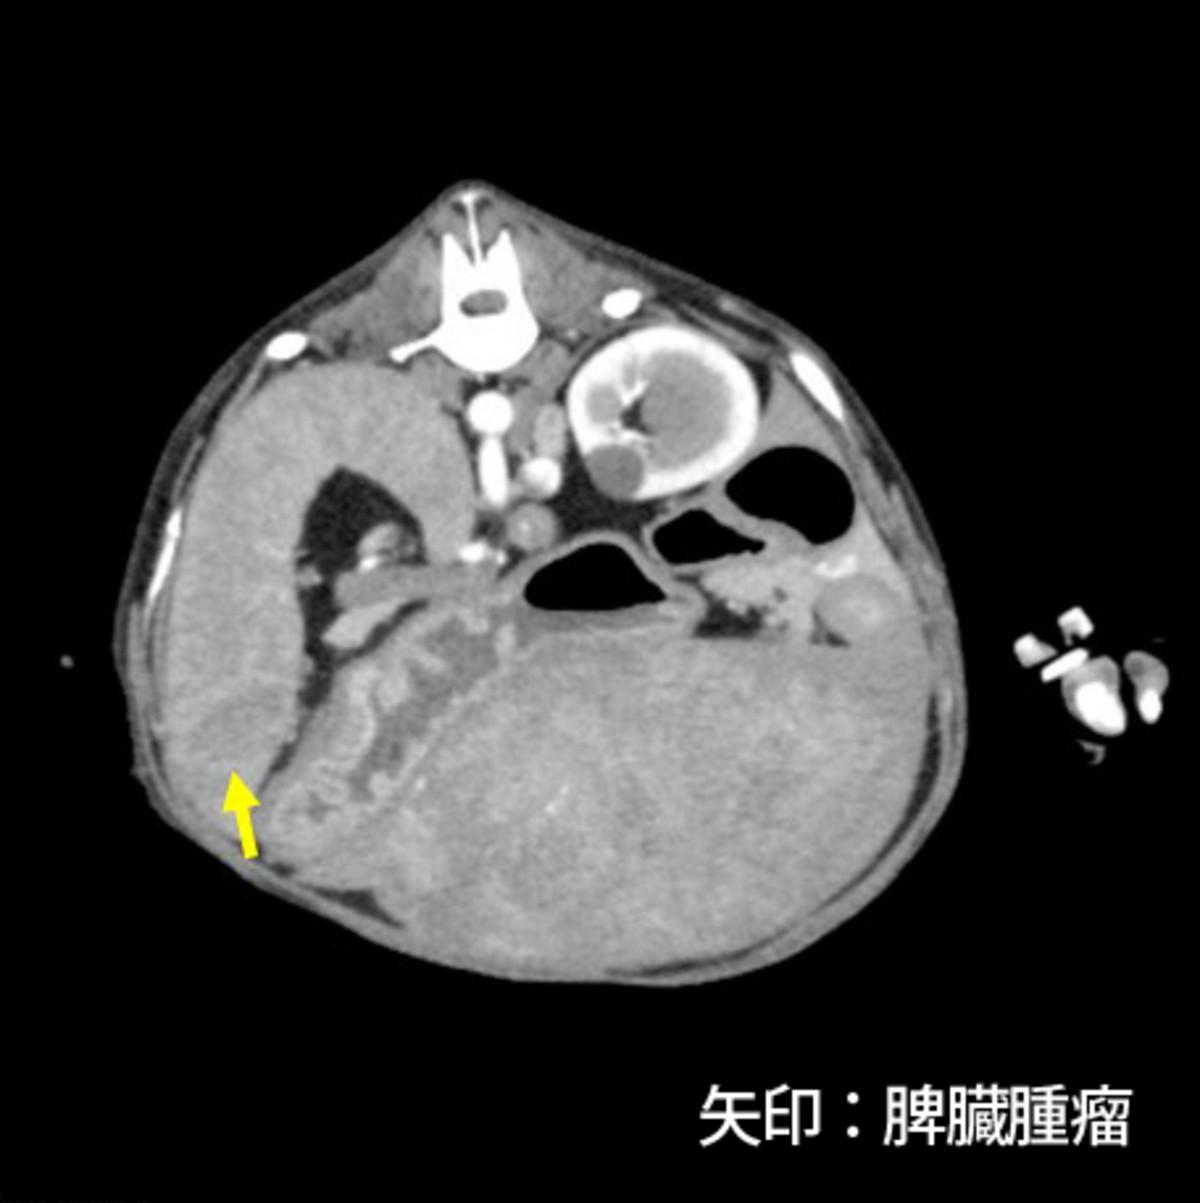

症例はミニチュア・ダックスフント、避妊雌、12歳11ヵ月齢、5.2kgです。当院初診の20日前に痙攣、失禁、意識の低下が5分ほど持続し、近医を受診しています。院内の検査にて低血糖(41mg/dL)、インスリンの低値、肝臓腫瘤を認め、ACTH刺激試験の結果から副腎皮質機能低下症は除外され、頻回の食事と糖液の投与により一般状態を維持していました。初診時の血液検査では低血糖(36mg/dL)および肝臓内側左葉に腫瘤を認め、糖液を経口投与してからCT検査を行いました。CT検査では肝臓の内側左葉(長径90mm)、外側左葉、尾状葉に多発性の腫瘤を認め、脾臓にも腫瘤(長径15mm)を認めました(図3)。肝臓原発の腫瘍および腫瘍に随伴する低血糖と診断し、根治は不可能であるものの臨床症状およびQOLの改善を目的とした手術が予定されました。

図3.CT検査にて多発性の肝臓腫瘤(図3-1、3-2)、脾臓腫瘤(図3-3)を認めた